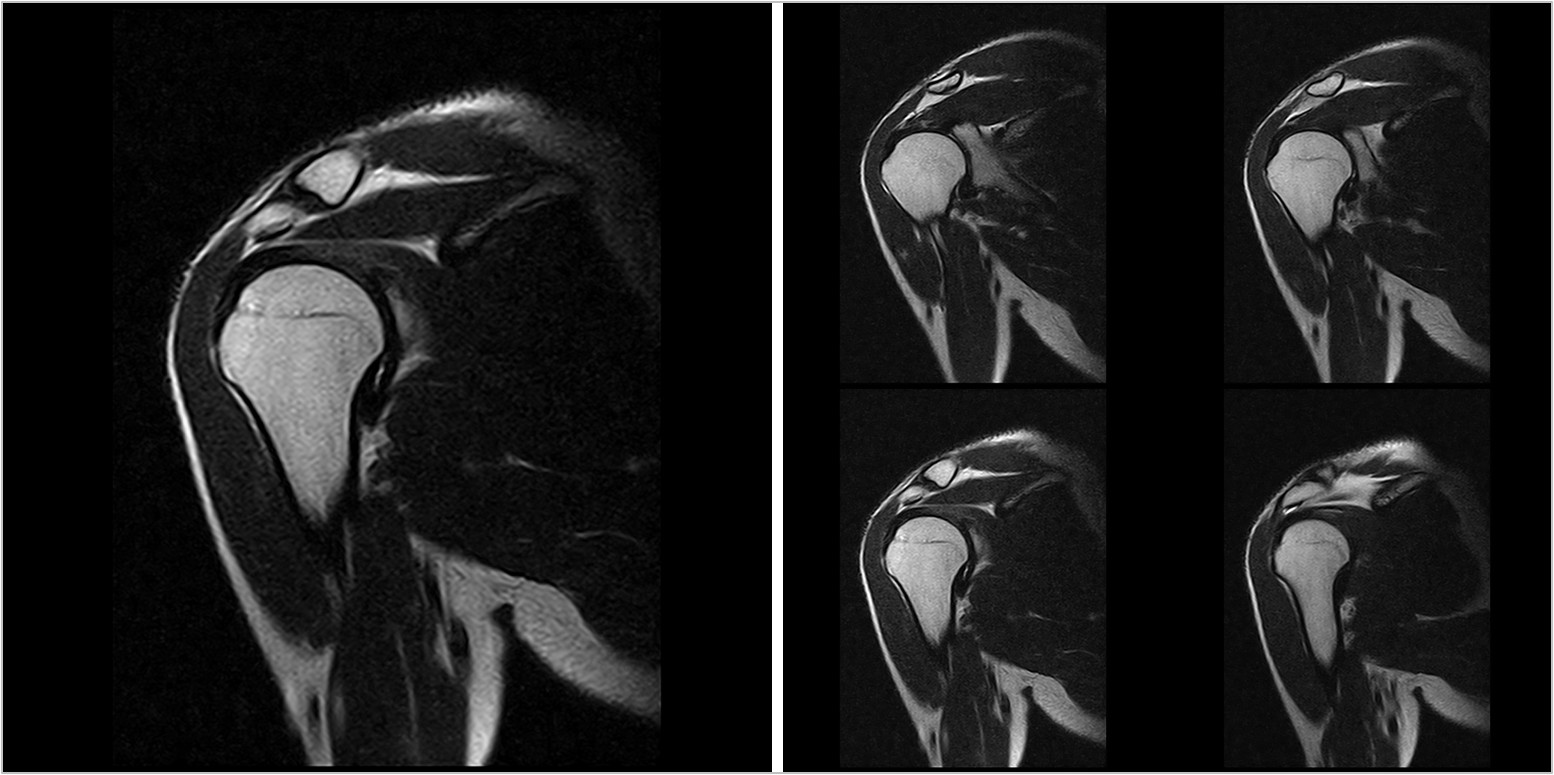

Hình ảnh lâm sàng

Giải pháp lâm sàng ấn tượng